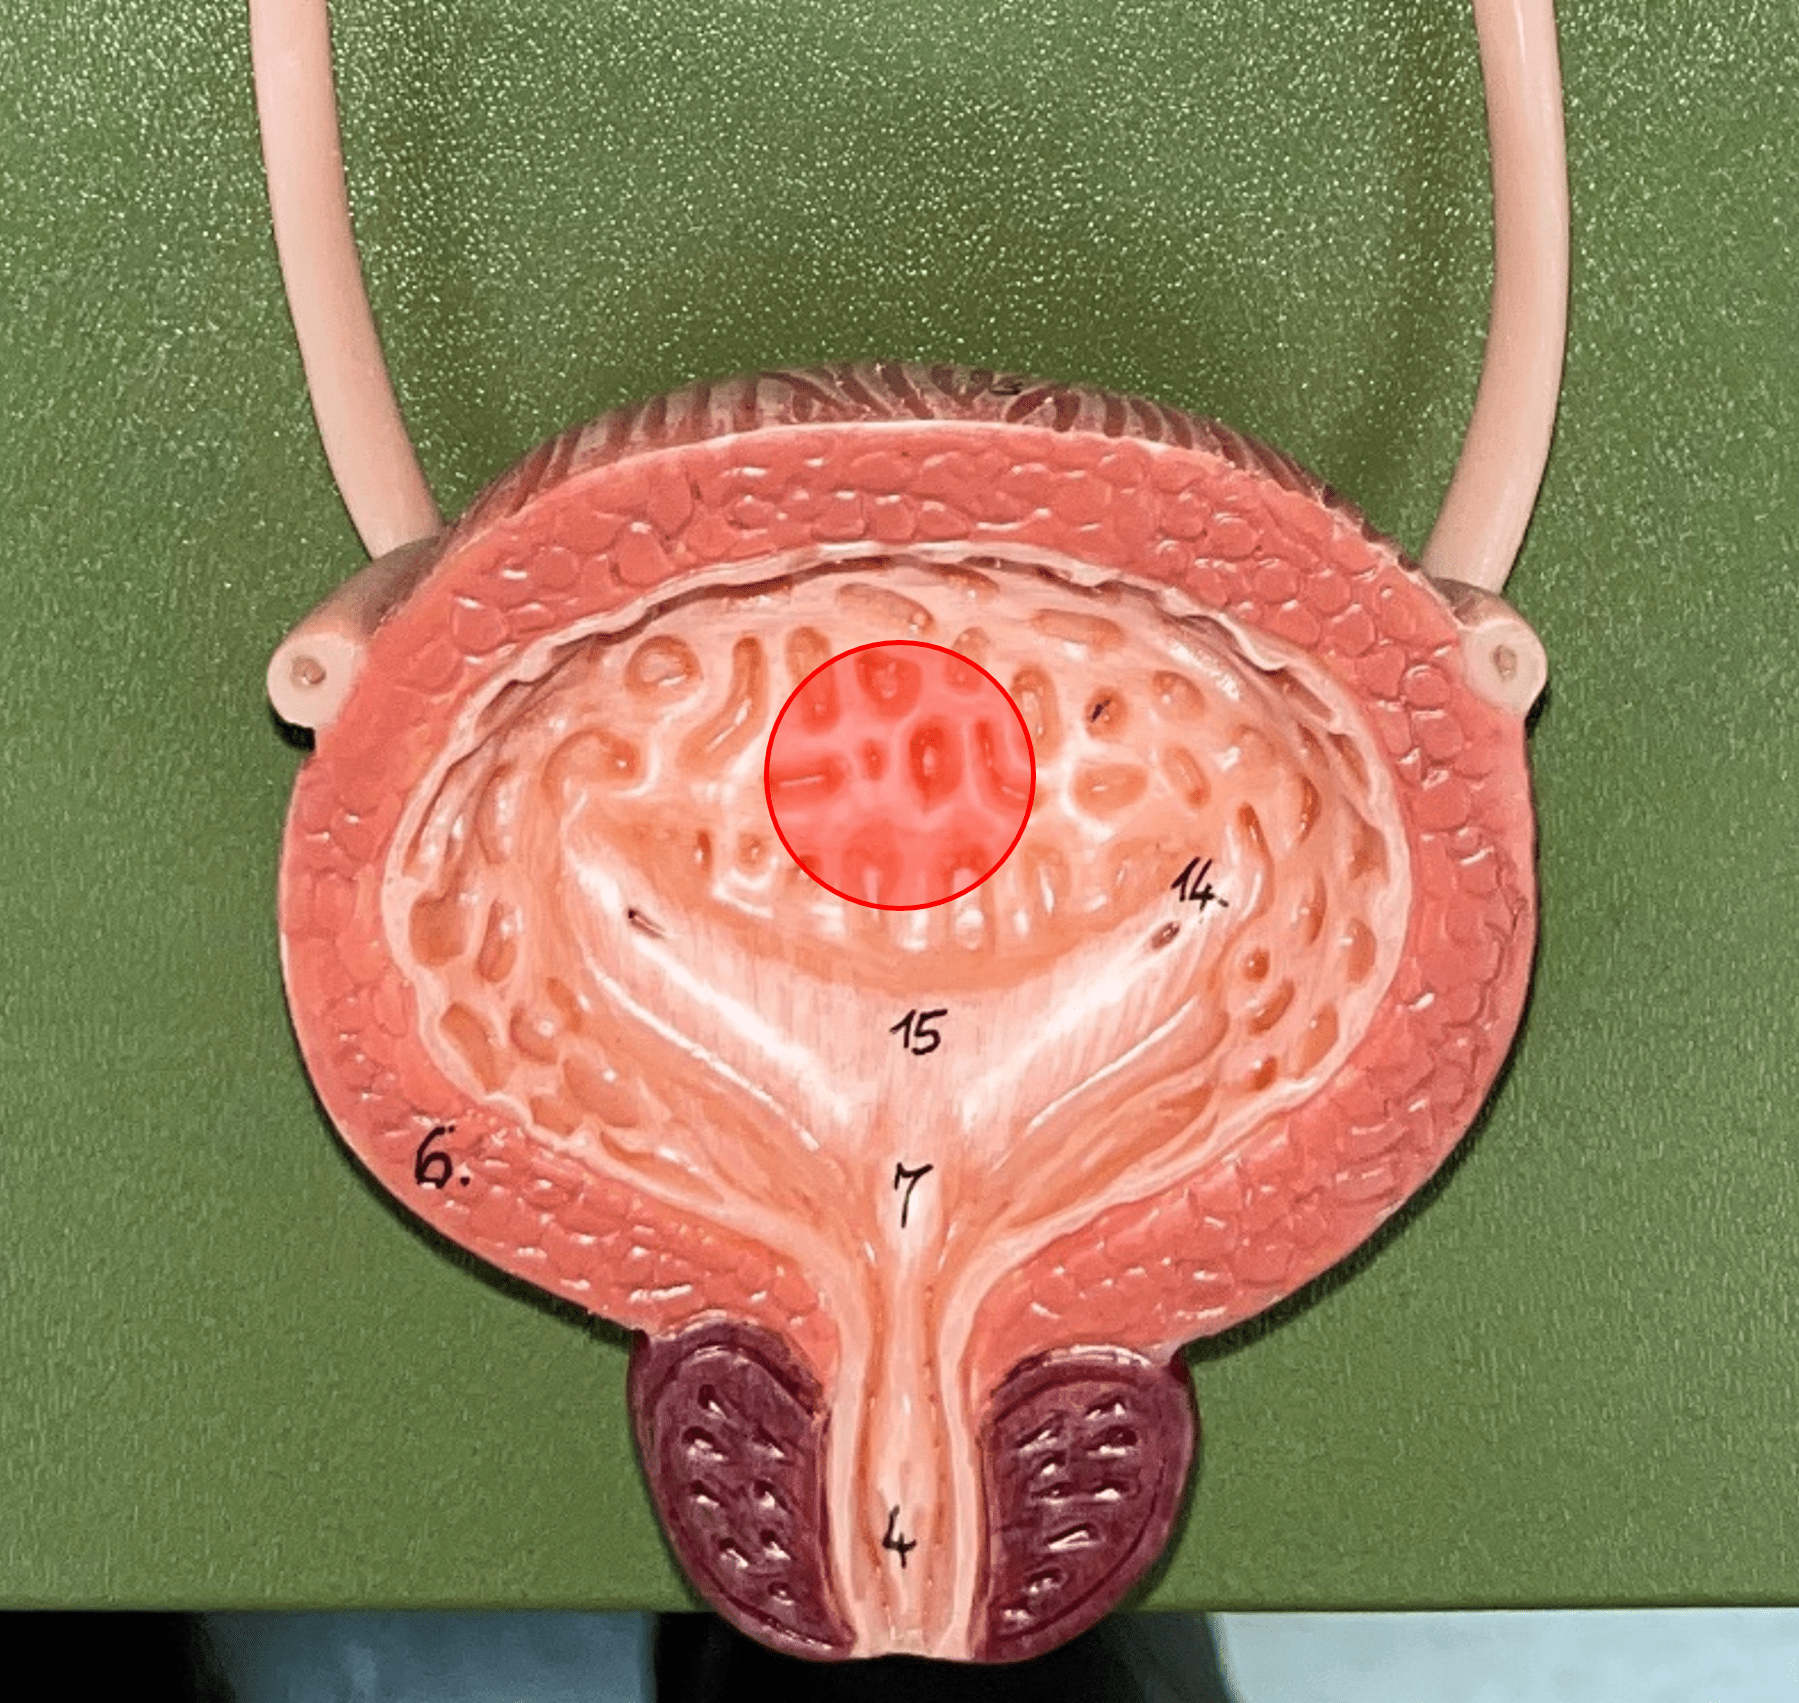

urinary bladder

The hollow sac organ that collects and temporarily stores urine.

27

New cards

rugae

• Part of the urinary bladder.

• Folds of the mucous membrane of the bladder.

• Flattens as the bladder fills with urine to increase capacity.

• Folds of the mucous membrane of the bladder.

• Flattens as the bladder fills with urine to increase capacity.

28

New cards

trigone

• Part of the urinary bladder.

• The triangle formed by the ureteral openings and internal urethra orifice.

• The triangle formed by the ureteral openings and internal urethra orifice.

29

New cards

ureteral opening

• Part of the urinary bladder.

• A posterior opening on either side of the of the bladder led in by the ureters.

• A posterior opening on either side of the of the bladder led in by the ureters.

30

New cards

internal urethral orifice

• Part of the urinary bladder.

• The anterior opening of the bladder leading to the urethra.

• The anterior opening of the bladder leading to the urethra.

31

New cards

detrusor muscle

• Part of the urinary bladder.

• The muscularis of the bladder.

• Contracts to expel urine from the bladder.

• The muscularis of the bladder.

• Contracts to expel urine from the bladder.

32